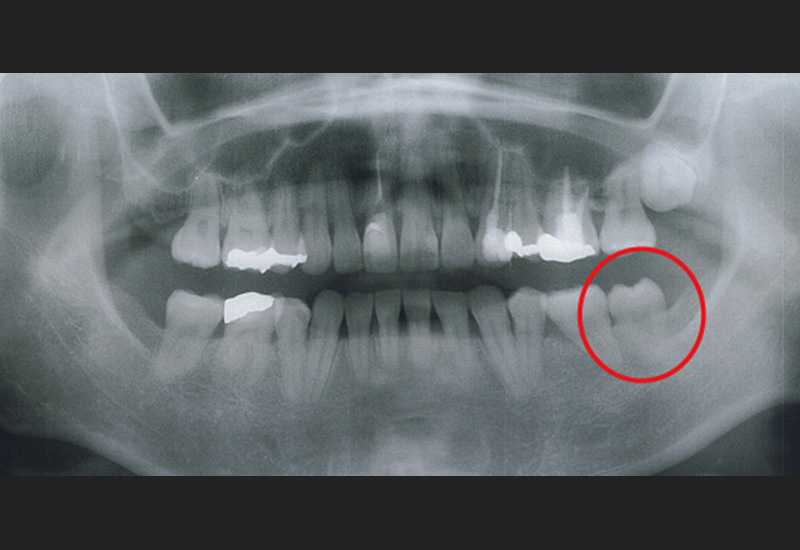

Case4 / 下右第1大臼歯欠損・下右親知らず埋伏

治療前

治療後

| 主訴 | 下右第1大臼歯欠損 下右親知らず埋伏 |

|---|---|

| 治療内容 | 倒れている下右親知らずを起こし、3D-LST矯正治療法を用い奥歯を大胆に移動。 |

| 患者年代・治療期間 | 30代女性・2年4ヶ月(難治症例) |